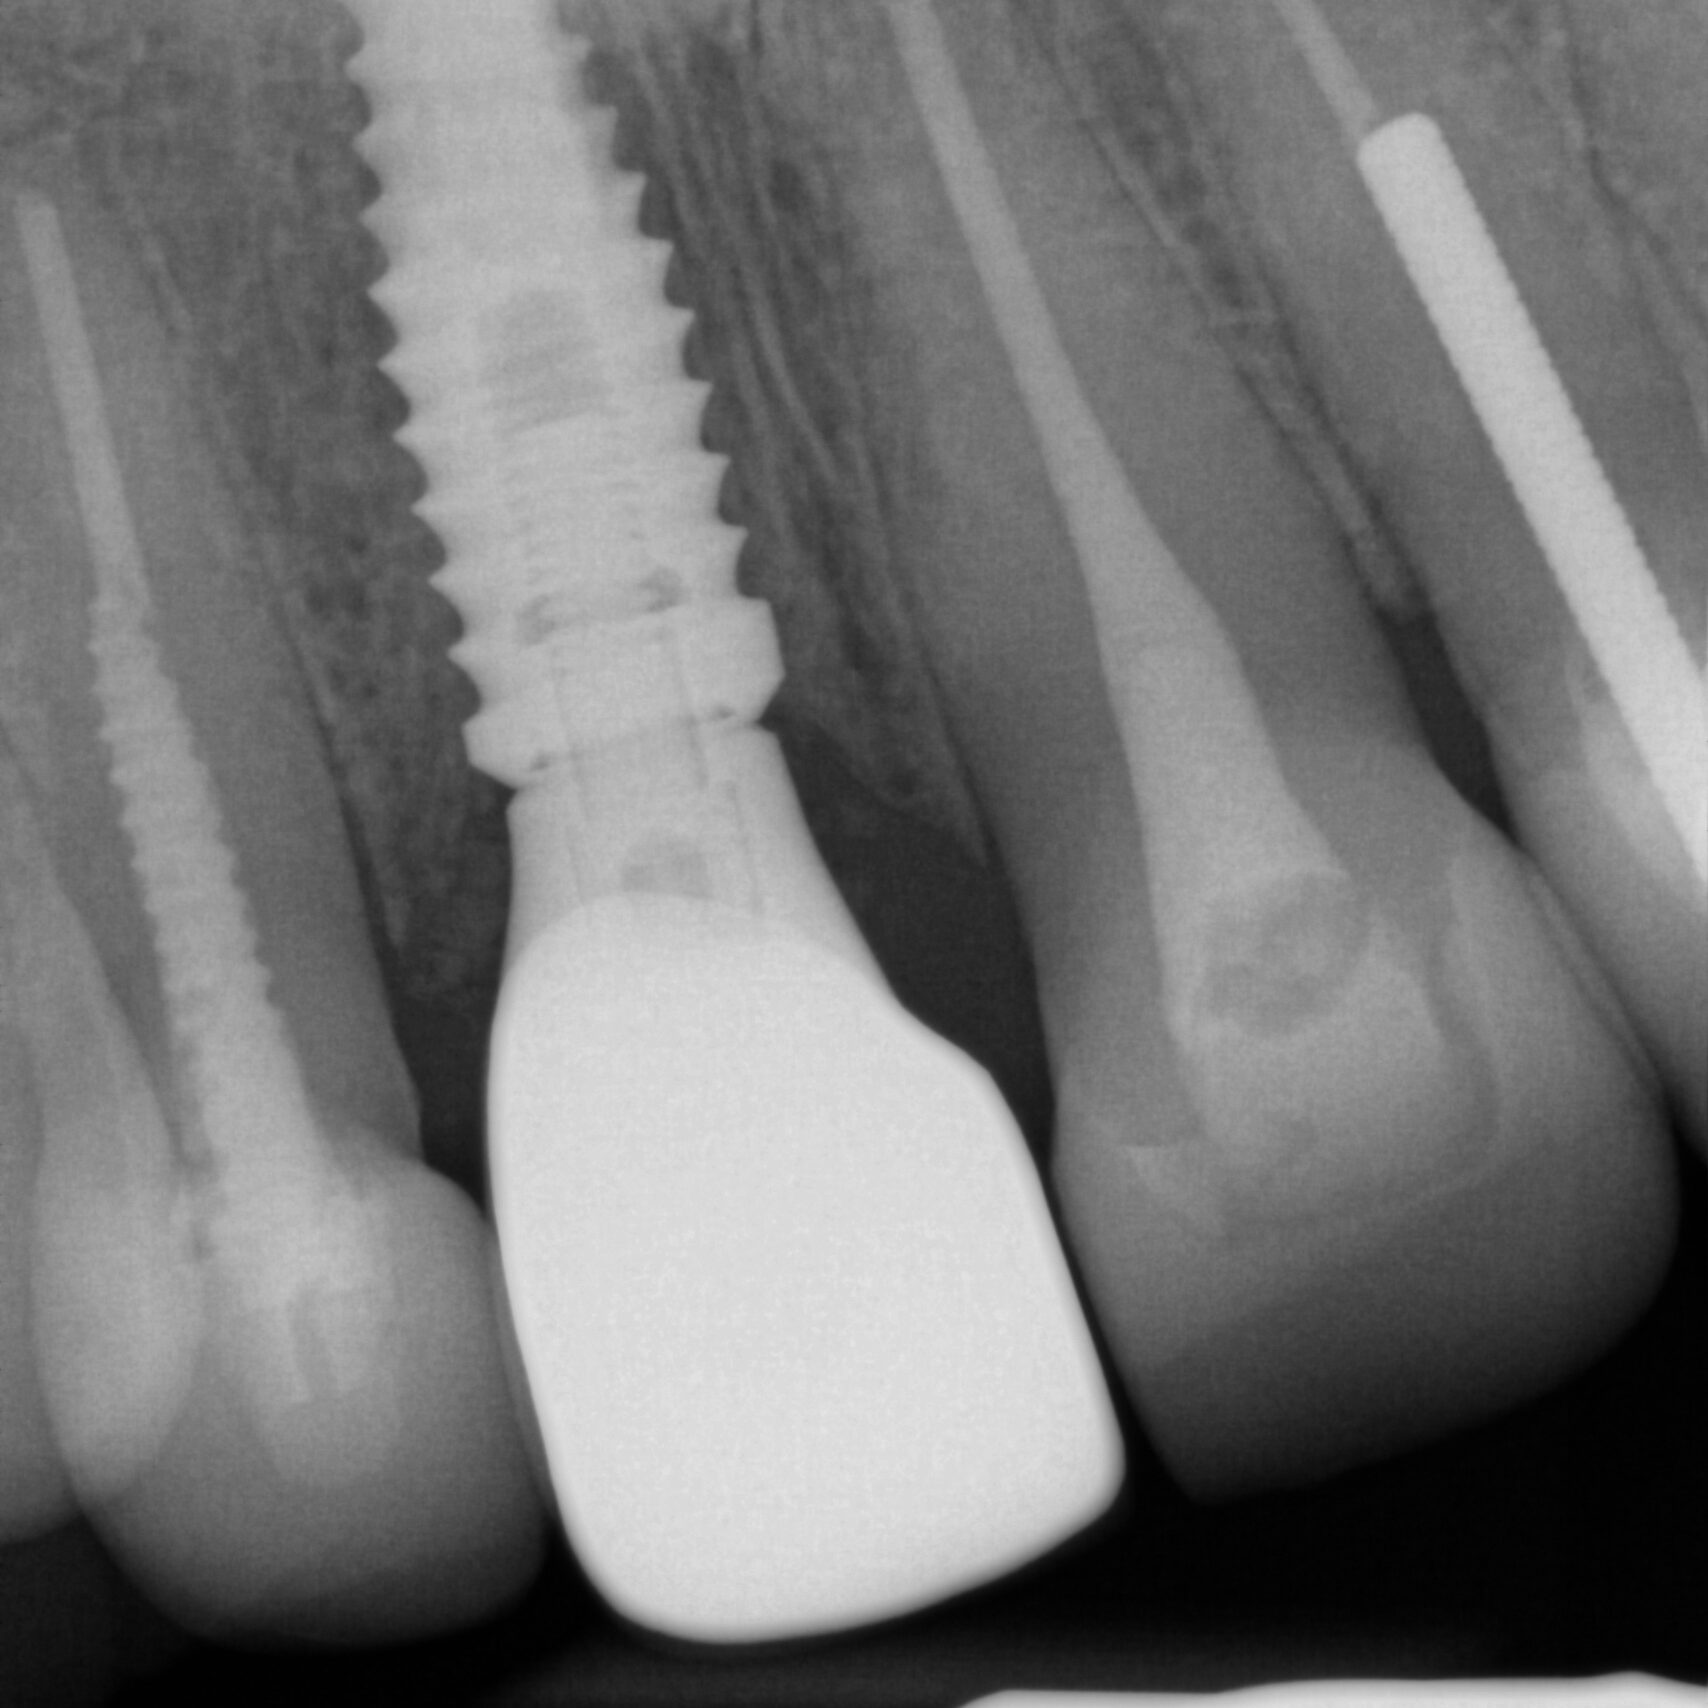

X-rays, or dental radiographs, can help detect and diagnose dental issues early. Two types of x-rays might be recommended during your routine exam. The panorex or full face x-ray is generally recommended every five years. A panorex allows your dentist to visualize the jaw bones, sinuses, roots of the teeth and other head and neck anatomy. Your dentist is trained to detect abnormalities and will let you know if he sees something that requires attention. Bitewing x-rays are generally recommended every 1-2 years. Bitewings can help detect cavities, especially when they are small and in between teeth. Finding cavities when they are small can prevent the need for more expensive dental treatments such as crowns or root canals. Bitewing x-rays also help your dentist visualize the supporting bone around your teeth. Detecting the loss of bone around teeth early is important to maintaining healthy gums.